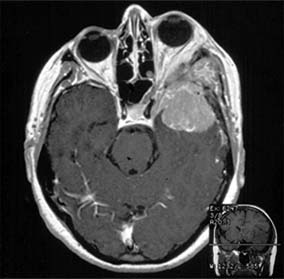

Intracranial meningiomas that may compress the optic nerve include those arising from the sphenoid wing, the tuberculum sellae (suprasellar meningioma), and the olfactory groove. Sphenoid wing meningiomas also produce proptosis, ocular motility disturbance, and trigeminal sensory loss (Figure 14-18). Surgical excision is generally effective in debulking intracranial meningiomas, but complete excision is often very difficult to achieve and recurrence rates are relatively high. Radiotherapy may be indicated as adjuvant or primary treatment. Pituitary adenoma and craniopharyngioma are discussed in the section on chiasmal disease (see below). The management of orbital causes of optic nerve compression is discussed in Chapter 13.

Figure 14-18

Figure 14-18: Axial MRI of sphenoid wing meningioma causing proptosis.